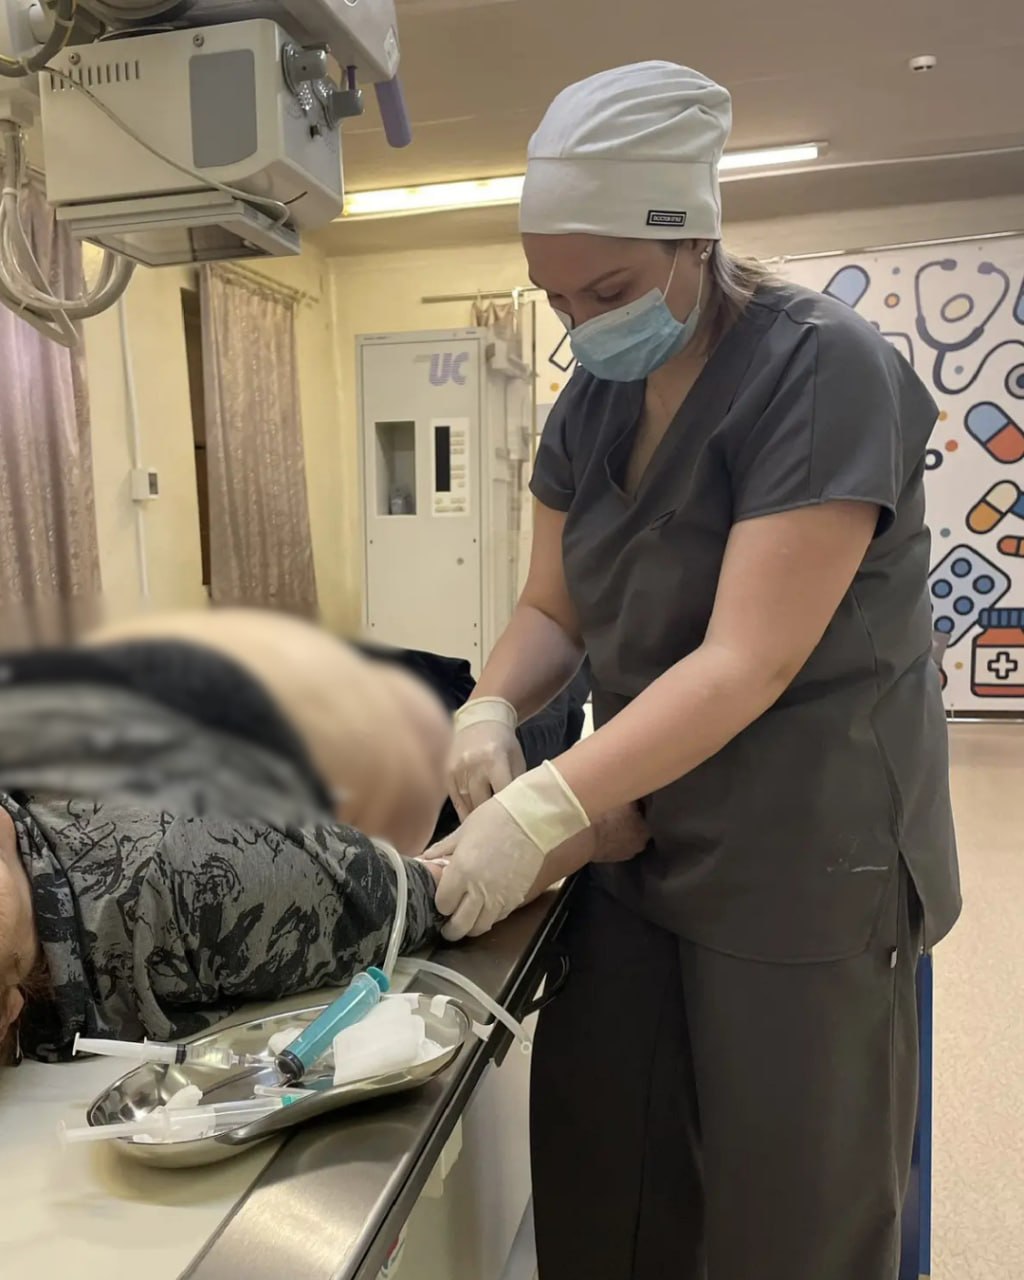

Впервые выполнили экскреторную урографию в Валдгеймской районной больнице ЕАО

В Валдгеймской районной больнице успешно проведена экскреторная урография. Исследование прошло в рамках комплексного ведения пациентки хирургического профиля и позволило уточнить диагноз без направления в специализированные центры.

Пациентка поступила в стационар с желчнокаменной болезнью. Ей была успешно проведена лапароскопическая холецистэктомия. В ходе послеоперационного обследования ультразвуковой метод выявил признаки, позволяющие заподозрить конкремент в правой почке, однако чёткой визуализации получить не удалось. Учитывая клиническую картину и лабораторные показатели, лечащая команда приняла решение провести экскреторную урографию.

Исследование прошло без осложнений и дало однозначный результат: крупного конкремента не выявлено. Если микрокамень и присутствует, его размер составляет около 0,3 см, он не накапливает контраст и локализован в чашечке почки. Пациентке рекомендовано динамическое наблюдение. На текущий момент её состояние стабильное, восстановление после основной операции идёт по плану.